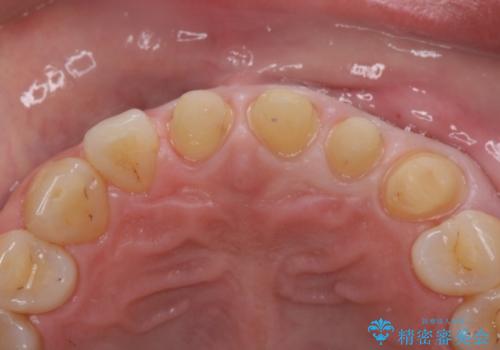

転んで前歯が欠けてぐらぐらに 歯の神経も死んでしまった

- 転倒して前歯を強打してかけてしまった、ぐらつくとのことで来院。

応急でみてもらった歯科医院で隣の歯と接着剤で留めてもらったとのこと。

歯の神経の状態を見たところ、前歯3本とも神経が死んでしまっていました。

根の治療を行い、ぐらつきに関しては様子を見て連結をするとのお話をさせていただきました。

結果ナイトガードの使用によりぐらつきはだいぶ回復してきたため連結はしていません。